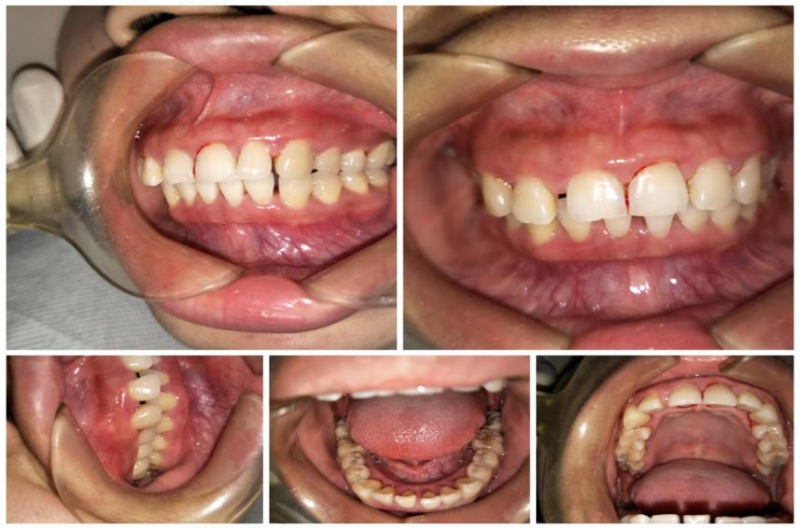

这天,涪陵区人民医院口腔科来了一位40岁的女性患者,她焦急地对医生说:“我刷牙出血有4年多了,吃饭出血、吃水果出血,刷牙更是出血多。这段时间更严重了,出现了不吃东西、未刷牙也出血的情况,严重影响我的工作和生活,医生,我是不是得了什么绝症啊?”经过医生仔细询问病史,开展口腔内检查,同时进行生命体征监测,发现患者口腔内牙龈明显红肿,轻轻触碰即可见鲜血溢出,见牙齿表面及牙龈深部覆盖大量牙结石、软垢,口臭明显。

通过对患者进行口腔全景片检查及全身系统性疾病(血源性疾病、肝功能异常及糖尿病病史等)排除后,口腔科诊断为:慢性牙周炎(中度),并制定针对性的治疗计划:序列牙周治疗。通过2次完善超声龈上洁治+超声、手工龈下刮治+手工根面平整等系列牙周基础治疗,1个月后患者的牙龈健康得到明显改善,牙龈不再出血,口臭也明显减轻。